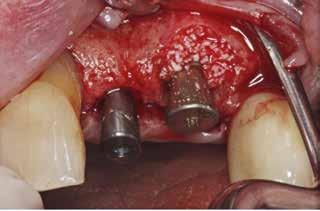

Klik ind på Tandlægebladet.dk og opret en reklamation, så sørger vi for, at bladet lander i din postkasse.

Klik ind på Tandlægebladet.dk og vælg om os

BAGGRUND – Transverselle okklusionsafvigelser kombineret med en vækstbetinget kæbedeformitet korrigeres sædvanligvis ved en sektioneret Le Fort 1-osteotomi eller kirurgisk assisteret ganeekspansion. Ved ekstreme transverselle skeletale diskrepanser mellem maksillen og mandiblen kan der være indikation for transversel udvidelse af mandiblen ved hjælp af mandibulær midtlinjeosteotomi eller mandibulær midtlinjedistraktionsosteogenese.

PATIENTTILFÆLDE – En 15-årig dreng med infantil autisme blev henvist fra Hjørring Kommunes Tandpleje til Kæbekirurgisk Afdeling, Aalborg Universitetshospital, for ortodontisk-kirurgisk behandling af et stort horisontalt maksillært overbid uden kontakt på nogen af tænderne. Den vækstbetingede kæbedeformitet blev korrigeret ved hjælp af ortodonti og mandibulær midtlinjedistraktionsosteogenese efterfulgt af en sektioneret Le Fort I-osteotomi og bilateral sagittal splitosteotomi.

KONKLUSION – Mandibulær midtlinjedistraktionsosteogenese er en forudsigelig behandlingsmodalitet til transversel udvidelse af mandiblen. Imidlertid er behandlingen forbundet med en betydelig risiko for recidiv samt biologiske og tekniske komplikationer, hvorfor mandibulær midtlinjedistraktionsosteogenese udelukkende anbefales til korrektion af ekstreme vækstbetingede transverselle okklusionsafvigelser.

EMNEORD Jaw abnormalities | malocclusion | orthodontics | orthognathic surgery

PERNILLE SAGBAKKEN, tandlæge, Odontologisk Institut, Det Sundhedsvidenskabelige Fakultet, Københavns Universitet

ANNETTE DALGAARD KJELLERUP, specialtandlæge i ortodonti, Kæbekirurgisk Afdeling, Aalborg Universitetshospital